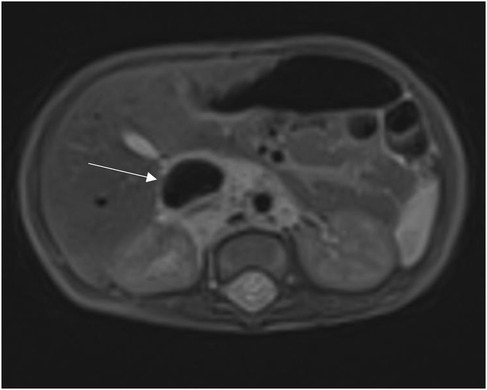

Given the high risk of heart failure persistence, we chose to use digital-subtracted angiography (DSA) to embolize vascular afferences to the lesion: via right femoral access, we performed an arteriography that demonstrated many arteriovenous fistulas inside the lesion with many lumbar and iliac vessels draining into IVC.

A single hypertrophic lumbar vessel was successfully selectively catheterized and embolized using 2 Concerto coils (2 mm × 4 cm and 2 mm × 6 cm, Figure 3).

X-ray image showing a catheter inserted into a blood vessel with an embolization coil deployed. The coil appears intricate and is designed to obstruct blood flow in a targeted area.

Figure 3. Coil embolization of hypertrophic lumbar vessel afferent to the lesion.